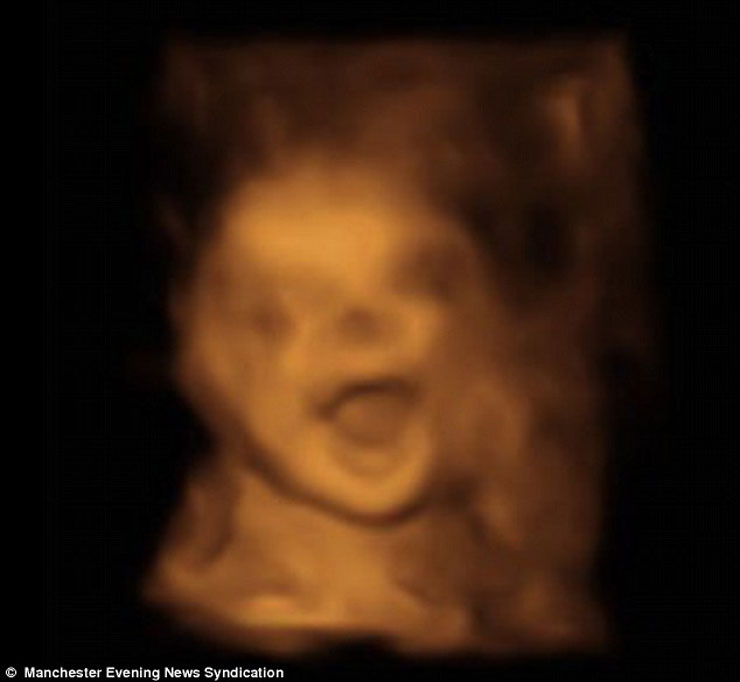

Ένα αγέννητο μωρό εμφανίζεται να… περνάει ευχάριστα και να γελάει μέσα στην κοιλιά της μητέρας του! Οι σχετικές φωτογραφίες που δημοσίευσε η Daily Mail δημιουργήθηκαν με τεχνολογία 4D η οποία είναι πλέον αρκετά δημοφιλής και αρχίζει να κερδίζει έδαφος συγκριτικά με το κοινό υπερηχογράφημα.

Oι μελλοντικοί γονείς δήλωσαν έκπληκτοι όταν είδαν τον γιο τους να τους χαμογελά, μέσα από την κοιλιά της μαμάς, κατά τη διάρκεια της 31ης εβδομάδας κύησης! Οι εικόνες είναι απλά… μαγικές: